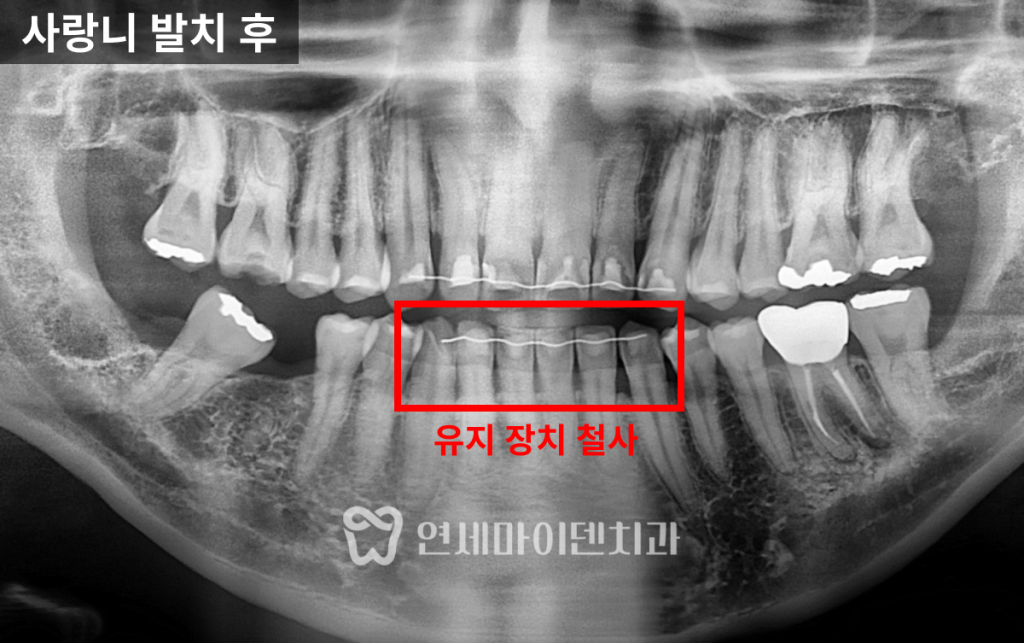

사랑니 발치 후 부분교정 시작

환자분은 과거에 전체 교정을 받으신 이력이 있어,

앞니 안쪽에는 유지장치 철사가 부착된 상태였습니다.

이 철사는 단단한 고정원이 되어,

부분교정의 기반으로 활용할 수 있었습니다.

부분교정은 필요한 부위만 선택적으로 치아를 움직이기 때문에,

고정원의 안정성 확보가 매우 중요합니다.

이번 케이스에서는

- 유지장치 철사를 고정원으로 사용하고,

- 미니스크류를 추가 식립하여 고정력을 강화했습니다.

이 과정을 통해 다른 치아의 불필요한 이동을 최소화하면서,

7번 어금니를 세워 임플란트 식립에 필요한 공간을

확보하는 것이 목표였습니다.